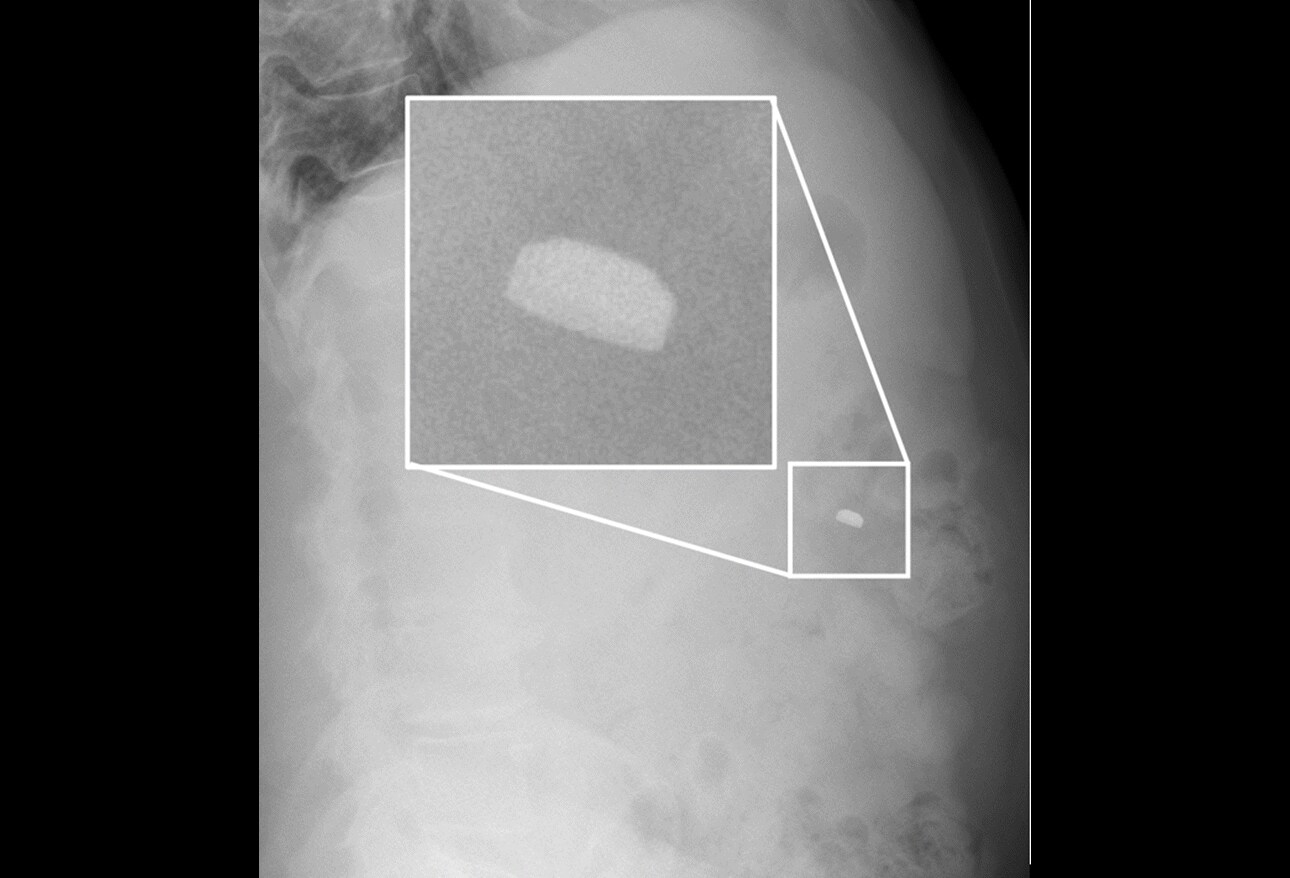

(a) Scout film male patient with rightsided flank pain. No radiopaque What Does No Radiopaque Foreign Body Mean Imaging is especially necessary following the removal of multiple foreign body pieces or when wound exploration is not possible. Imaging modalities that can be. Radiopaque foreign bodies can cause discomfort and potential health risks. Sequelae like emphysema, haematoma, foreign body granuloma, inflammatory reactions or even frank abscesses can provide further (albeit non. Understanding what they are, how they are. Mr. What Does No Radiopaque Foreign Body Mean.